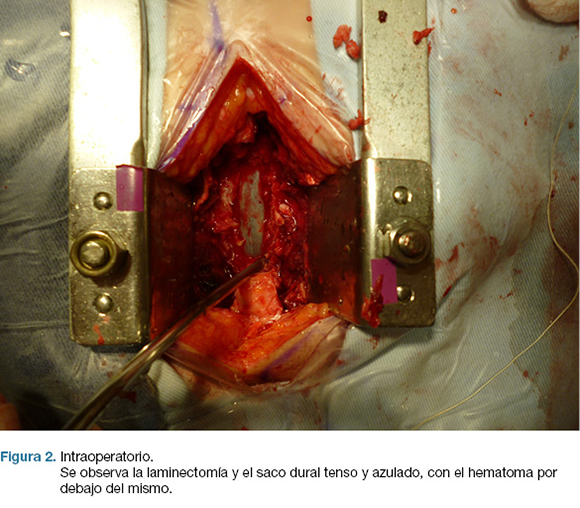

En la cirugía se realizó laminectomía T4-T6 exponiendo el saco dural. El mismo estaba tenso y azulado (figura 2) y al abrirlo, se encontró un hematoma subdural espinal, que se evacuó completamente (figuras 3).